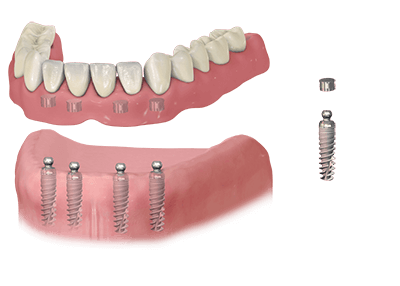

A fogászati implantátum egy olyan műgyökér, mellyel egy vagy több hiányzó fogat élethűen, stabilan és akár egy életre pótolni tudunk:

- Kicsi csavarszerű, menetes eszköz.

- Műtéti úton helyezik be az íny alá, az állcsontba.

- A titán implantátum mesterséges foggyökérként működik, erős alapot biztosít a pótfoghoz, fogászati hídhoz, de akár egy teljes körhídhoz és fix fogsorhoz is.

Gömbfejes műanyag fogsor – lokátoros fogsor – pattintós fogsor:

- Kivehető, de fixen rögzülő, magas minőségű, műanyag fogsor.

- 2 vagy 4 db implantátumra készül (alsó állcsont esetén akár 2db is elegendő lehet).

- A beültetett implantátumokban speciális felépítmények rögzülnek, melyek párja a fogsorba ágyazódik, kettejük összekapcsolódása biztosítja a fogsor rögzülését.

- Nincs szájpadlási rész, nincs hányinger.

- Könnyű a kivétele, egyszerű a kezelése, nincs szükség fogsorragasztóra.

- Megfelelő tartást ad, visszaadja a rágóképességet, megszűnnek a beszédzavarok.

- Éjjel is viselhető.